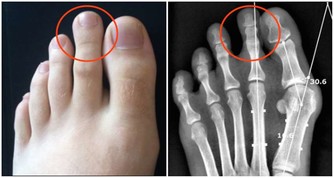

不想被痛風盯上,少吃2種食物,改掉1個壞習慣,自然啥事也沒有